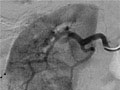

Durante una angiografía, el médico le introducirá un tubo delgado y flexible en un vaso sanguíneo en la ingle o el brazo. Este tubo se llama catéter. El médico guía el tubo hasta el vaso sanguíneo que se va a examinar. A continuación se inyecta un tinte a través del tubo para hacer que la zona sea más fácil de ver. Se toman radiografías o imágenes de la zona.

Se afeitará y limpiará el lugar donde se introducirá el catéter (en la ingle o por encima del codo). Su médico adormecerá la zona con anestesia local. Luego, el médico introducirá una aguja en el vaso sanguíneo. Se colocará una aguja guía a través de la aguja en el vaso sanguíneo y se retirará la aguja. El catéter se colocará sobre la aguja guía y será desplazado hasta el vaso sanguíneo. Luego, se guiará el catéter a través de los vasos sanguíneos hasta que la punta se encuentre en la zona que debe estudiarse. Su médico usará el radioscopio para observar el movimiento del catéter en los vasos sanguíneos.

Una vez que se haya colocado el catéter, se inyecta el material de contraste a través de él. Es posible que se le pida que inhale y contenga la respiración durante varios segundos. Se tomarán varias imágenes radiográficas, una tras otra. Estas estarán listas de inmediato para que su médico pueda observarlas. Debe permanecer muy quieto para que las imágenes sean nítidas. Es posible que se tomen más imágenes.